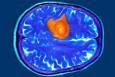

تومور مغزی

۷ نشانه مهمی که باورتان نمی‌شود نشان دهنده تومور مغزی هستند

۷ نشانه مهمی که باورتان نمی شود نشان دهنده تومور مغزی هستند

از فراموشی تا تغییر دست‌خط؛ ۷ نشانه مهم تومور مغزی که اغلب نادیده گرفته می‌شوند

۷ نشانه مهم تومور مغزی که اغلب نادیده گرفته می‌شوند